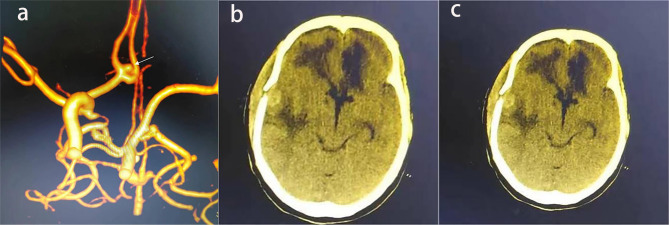

背景:颅内动脉瘤破裂合并颈内动脉闭塞(ICAO)是一种罕见且严重的血管疾病。我们的目的是描述这些患者的临床特征和结果。方法:回顾性分析中国多中心动脉瘤数据库(CMAD)中RIA合并自发性ICAO的病例。采用Logistic回归分析确定与患者预后相关的独立危险因素。采用Cox比例风险模型确定累积死亡率的预测因子。结果:我们分析了52例伴有ICAO的RIA,其中单侧41例,双侧11例。单侧ICAO病例中,同侧8例,对侧16例,中线17例。治疗包括绕线31例,夹持6例,保守处理15例。26例预后良好,17例预后不良,包括12例死亡。Logistic回归发现Hunt-Hess分级IV-V、保守治疗和症状性脑梗死是不良结局的独立危险因素。Cox比例风险模型发现Hunt-Hess分级IV-V是2年随访期间死亡率的预测因子。结论:Hunt-Hess分级、治疗和住院脑梗死独立预测不良结局,IV-V级与早期死亡相关。ICAO可能增加动脉瘤破裂的风险,突出了动脉瘤位置及其相关血流动力学机制在临床管理中的重要性。

Results: We analyzed 52 cases of RIA with ICAO, including 41 unilateral and 11 bilateral cases. Among unilateral ICAO cases, aneurysms were ipsilateral in 8, contralateral in 16, and midline in 17. Treatment included coiling (31 cases), clipping (6 cases), and conservative management (15 cases). Prognosis was favorable in 26 cases and unfavorable in 17, including 12 deaths. Logistic regression identified Hunt-Hess grade IV-V, conservative treatment, and symptomatic cerebral infarction as independent risk factors for unfavorable outcome. Cox proportional hazards model found Hunt-Hess grade IV-V to be a predictor of mortality during the 2-year follow-up.

Conclusion: Hunt-Hess grade, treatment, and in-hospital cerebral infarction independently predict unfavorable outcome, with grades IV-V linked to early death. ICAO may increase the risk of aneurysm rupture, highlighting the importance of aneurysm location and its related hemodynamic mechanisms in clinical management.